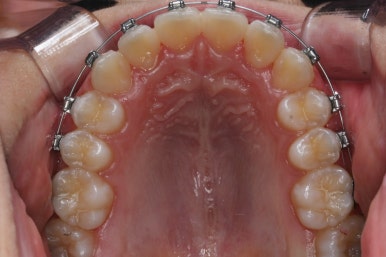

키다리아저씨치과에서 부산비발치교정 전후 사진 비교입니다.

치료 종료 시점에는 위아래 앞니 모두 안쪽에 유지장치를 붙이고 있는 것을 볼 수 있습니다.

교정 중에 양치가 잘 되지 않아 치료 후 모습에서 잇몸이 부어있는 모습도 보이는데 양치질을 잘 해주면 금방 좋아질 수 있습니다.

앞니가 매우 가지런해졌고 예뻐졌네요.

악궁확장장치 기간까지 포함하여 총 1년 4개월이 걸렸습니다.